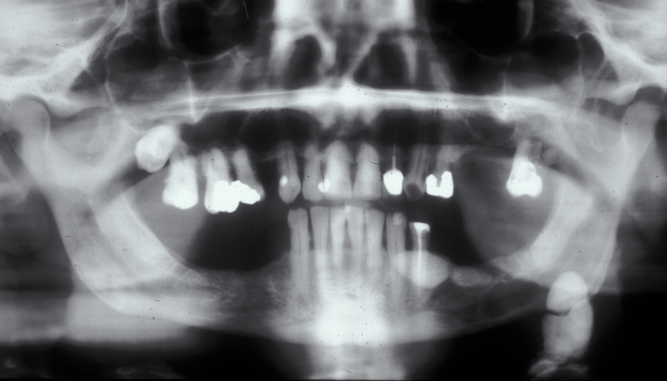

Approximately 80 % of salivary calculi occur in the ductal system of the submandibular glands. This is due to the greater length of the duct, its upward course and the thicker mucus secreted by the submandibular glands. There will usually be a history of painful, recurrent swelling in the submandibular region, particularly associated with eating or the anticipation of eating (pre-prandial swelling). Plain (X-ray) radiography will usually demonstrate a calculus in the duct (see Figure 1), or in the junction of the duct and gland or the gland itself (see Figure 2).

Figure 2: Calculi in the duct and the submandibular gland.